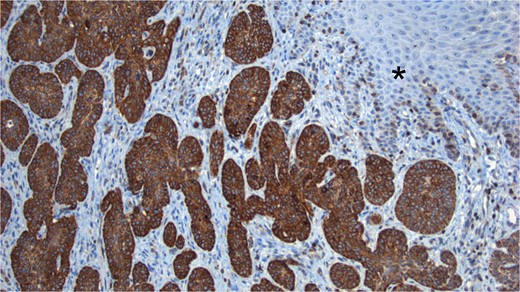

The sample was sent to pathology for consultation, where the provisional diagnosis was identified as ‘pigmented basaloid carcinoma.’ Microscopically, the hematoxylin and eosin-stained sections revealed a malignant tumor characterized by nests of cells with scant to moderate cytoplasm and basophilic nuclei, exhibiting peripheral nuclear palisading. Melanocytes and melanin pigment were observed within the tumor nests and stroma. Immunohistochemical tests showed positive results for p63 and CK5/6 (Fig. 1), and negative results for HMB-45. Additionally, intense and diffuse positivity for BCL2 was noted (Fig. 2). The final diagnosis confirmed a pigmented basal cell carcinoma with infiltrative, micronodular, and ulcerative patterns.

BCL2 Staining. Tumor cells show intense positivity for BCL2, contrasting with the negativity observed in the normal skin (*).